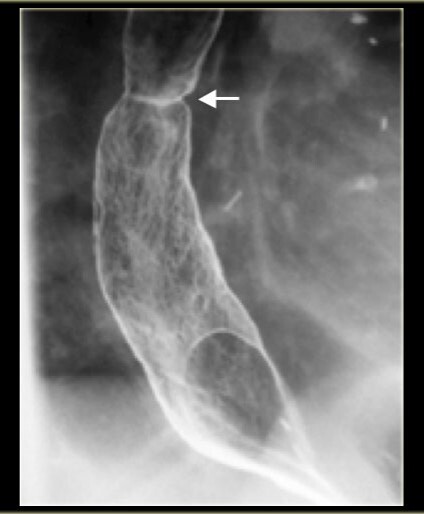

What pathology is shown here?

Esophageal Atresia

Tracheaoesophageal fistula

What are the white arrows pointing to?

The airway

What are the radiographic signs of a Tracheoesophageal Fistula?

A

-Connection of the fistula between airway and esophagus

-Large dilation of the esophagus